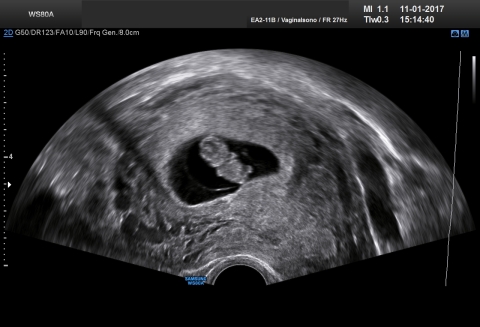

Im Ultraschall-Video aus der 8. Schwangerschaftswoche sind Extremitäten wie auch Gesicht schon gut erkennbar, auch wenn der Embryo erst ca. 15 mm misst! Die Aufnahme entstand in der Praxis Gyné am See in Küsnacht ZH.

Grösse des Embryos (Scheitel-Steiss-Länge): 14-16 mm

Gewicht: 2 g

Die Finger und Zehen sind nun deutlich zu sehen. Die Oberlippe sowie die Nasenspitze werden gebildet. Die Augenlider werden sichtbar. Am Ende der 8. Woche sind alle inneren und äusseren Organe angelegt und einige schon recht weit entwickelt, zum Teil funktionieren sie bereits.